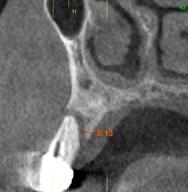

Presentamos el caso de un paciente varón de 57 años que acude a la consulta demandando tratamiento dental para sustituir sus prótesis removibles superiores por una rehabilitación implantosoportada. Presenta un esquelético superior que se sustenta sobre los caninos (13 y 23), existiendo movilidad en la pieza 13 y dolor. En las imágenes iniciales podemos observar el estado de desajuste en el que se encuentra el esquelético y la afectación de la pieza 13 donde se objetiva una recesión que deja al descubierto parte de la raíz dental (Figura 1-4). En la radiografía panorámica inicial se observa un defecto circunferencial grave en el canino superior derecho y una neumatización excesiva de ambos senos

maxilares, lo que apunta a la existencia de una atrofia vertical ósea excesiva en esta área que pretende ser rehabilitada con implantes dentales (Figura 5). A mayor aumento vemos la fractura radicular de la pieza 13 que ha generado el defecto circunferencial (Figura 6) y en el cone beam de planificación se constata y además se pone de manifiesto la dimensión del defecto óseo y el volumen óseo residual a nivel palatino de 2 mm (Figura 7).

Figura 5. Radiografía inicial del paciente. En ella observamos el defecto crateriforme del diente 13 y una neumatización excesiva de ambos senos maxilares en el maxilar posterior donde se pretenden realizar implantes dentales. Figura 6. Imagen en detalle de la pieza 13. En esta imagen cercana podemos observar una fractura vertical evidente en el área del ápice ya en este tipo de prueba radiológica. Figura 7. En el cone-beam de planificación se objetiva la fractura y el defecto crateriforme con pérdida de la tabla vestibular completa y un remanente óseo a nivel palatino de 2 mm para la posterior inserción de un nuevo implante.